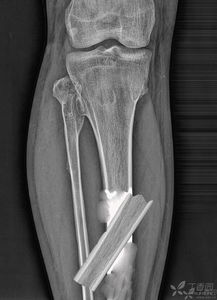

診斷手段:主要是根據(jù)臨床表現(xiàn)加上影像學檢查診斷。 (1) X線片:凡懷疑骨折者應(yīng)常規(guī)行X線檢查。

可發(fā)現(xiàn)臨床上難以發(fā)現(xiàn)的不完全骨折、深部骨折、關(guān)節(jié)內(nèi)骨折和撕脫骨折,臨床上明確骨折者也應(yīng)行X線檢查明確骨折類型及具體 情況,以指導(dǎo)治療。 (2) CT:對于骨折不明確但又不能排除者、脊柱骨折可能壓迫脊髓神經(jīng)根者及復(fù)雜骨折者 均應(yīng)行CT檢查。